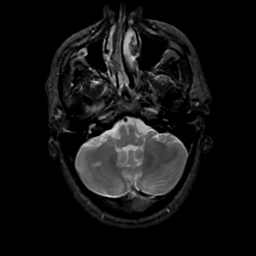

MR Study #16, June 23, 1991 -- Slice #10